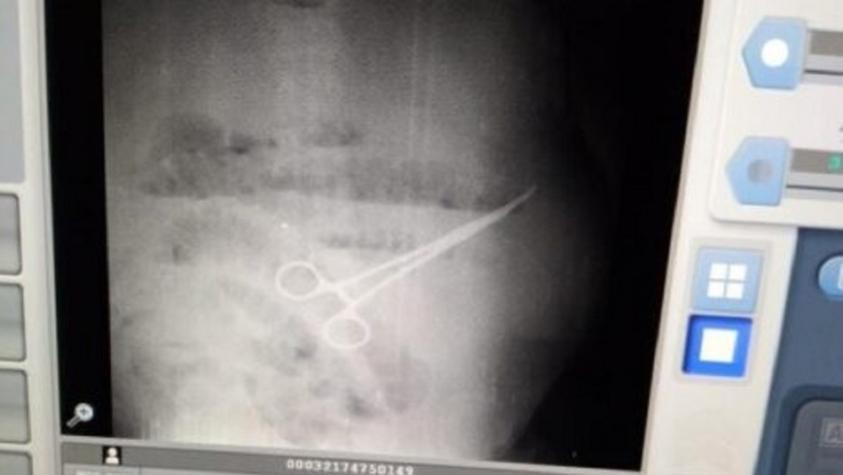

Trabajador murió tras negligencia médica: Dejaron una tijera en su estómago